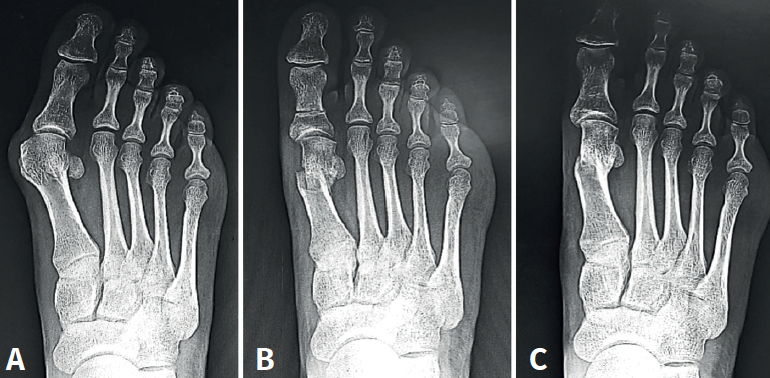

Mediante abordaje de 5 mm a nivel plantar proximal al bunion se realiza capsulotomía y exostectomía (Figuras 1A, B y C). Por otro abordaje de 3 mm realizado a 5 mm dorsal y distal del primero y a 15 o 20 mm proximal a la superficie articular (entre 7 y 10 mm del centro geométrico de la cabeza), extraarticular y equidistante a la cortical dorsal y plantar, se procede al tallado de la osteotomía de Chevron con fresa Isham larga (2,0 × 12 × 65 mm), (Figura 1D). Con la fresa dirigida, preferentemente, perpendicular al cuarto metatarsiano y llevándola ligeramente a plantar o dorsal según quisiéramos descender o elevar, respectivamente, la cabeza metatarsiana, perforamos el primer metatarsiano. En modelos sin fijación, elegimos esta dirección hacia proximal para lograr un leve acortamiento, que relaja la articulación metatarsofalángica y reduce las posibilidades de pérdida de corrección de la cabeza (Figura 2). En modelos con fijación se dirige más hacia distal, con referencia en la diáfisis del segundo metatarsiano o incluso perpendicular al primer rayo. Realizamos el corte dorsal casi vertical y el corte plantar lo más horizontal posible (paralelo al suelo), con dirección de distal a proximal, tratando de que esta rama sea más larga que la anterior. Se puede lograr de forma adicional corrección del DMAA. Una vez completa la osteotomía, se desplaza a lateral manualmente bajo visión radioscópica hasta que se logra una posición satisfactoria. No se coloca osteosíntesis. Se procede a la adición de otros gestos percutáneos de ser necesarios (liberación lateral de partes blandas, osteotomía de Akin, osteotomías de metatarsianos o dedos menores) (Figura 3).